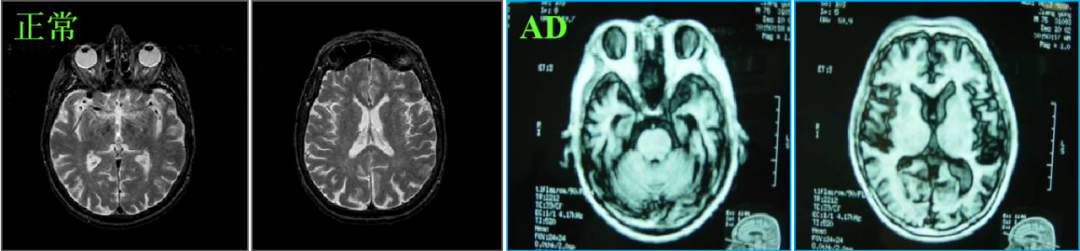

当前,阿尔茨海默症的诊断主要靠两种检测方法,一种是脑脊液AD标志物检测,另一种是通过PET扫描仪的脑成像检测。在2018版的权威指南里,已将这两种检测作为诊断阿尔茨海默病的“金标准”。

脑脊液AD标志物检测需要做腰椎穿刺术获取脑脊液,这种检查虽然准确性较好,但是由于标本获取过程复杂,患者创伤大。

PET检查需要在血液内注入放射性物质,然后再做脑扫描,需要做3次,对身体也有一定的损伤,而且价格昂贵。

▲PET扫描显示结果